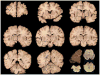

Context: Autopsy evaluation of the brain of a patient with frontotemporal dementia (FTD) can be daunting to the general pathologist. At some point in their training, most pathologists learn about Pick disease, and can recognize Pick bodies, the morphologic hallmark of Pick disease. Pick disease is a type of frontotemporal lobar degeneration (FTLD), the general category of pathologic process underlying most cases of FTD. The 2 major categories of pathologic FTLD are tauopathies (FTLD-tau) and ubiquitinopathies (FTLD-U). Pick disease is one of the FTLD-tau subtypes and is termed FTLD-tau (PiD).

Objective: To "demystify" FTLDs, and to demonstrate that subtypes of FTLD-tau and FTLD-U can be easily determined by following a logical, stepwise, histochemical, and immunohistochemical investigation of the FTD autopsy brain.